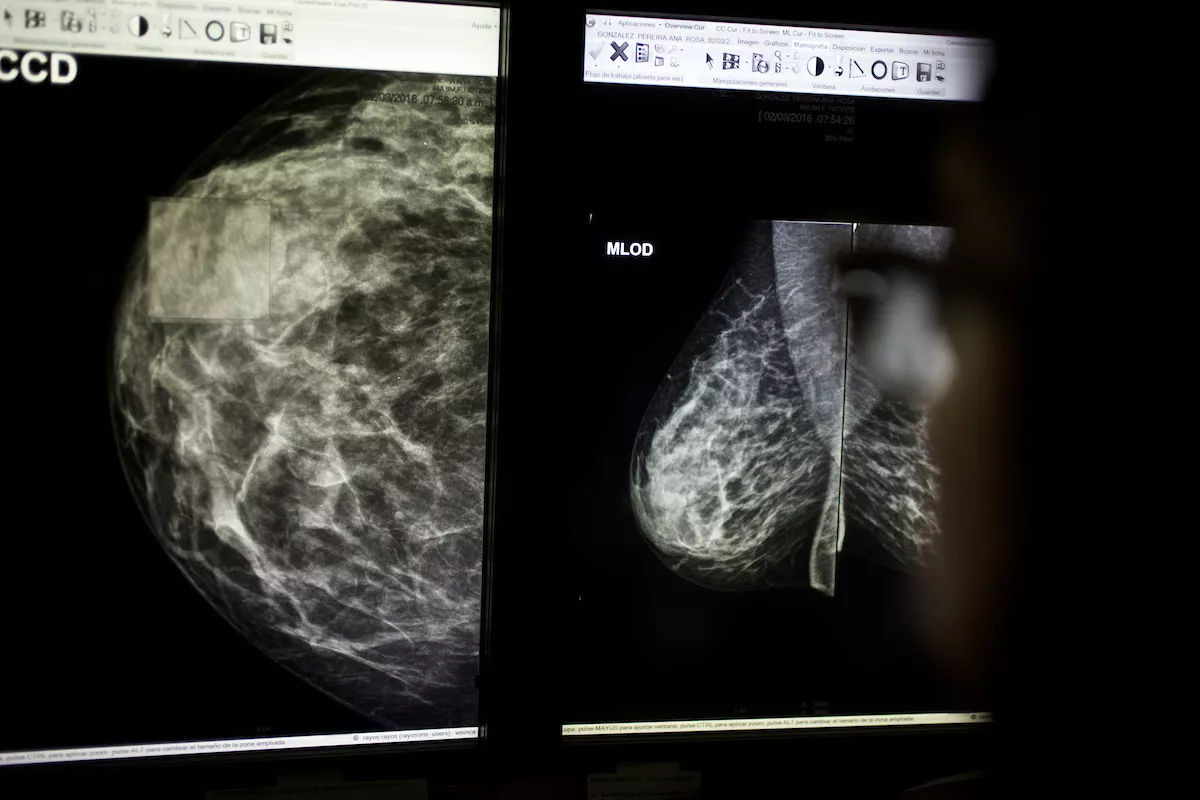

Este 19 de octubre es el Día Mundial de Lucha Contra el Cáncer de Mama. Se desarrolla una jornada de mamografías en el Hospital Maciel para usuarias de ASSE y también se realizó el acto oficial, en el Ministerio de Salud Pública, con la participación de la vicepresidenta Beatriz Argimón y del ministro Daniel Salinas.

El Ministerio recuerda en su web que el cáncer de mama es el más frecuente en las mujeres uruguayas. Se estima que 1 de cada 11 mujeres uruguayas podría desarrollar cáncer de mama en algún momento de su vida. El 1% de los cánceres de mama se presentan en hombres.

Se diagnostican en promedio aproximadamente 2000 nuevos casos por año. De acuerdo con las cifras del Ministerio de Salud Pública, cada año mueren aproximadamente 700 mujeres por esta causa.

«Al igual que sucede con muchos cánceres, la probabilidad de desarrollar cáncer de mama aumenta con la edad. En nuestro país, el 78 % se presenta en mujeres mayores de 50 años y aproximadamente un 5.5% de los casos se presenta en mujeres menores de 40 años. Los factores que aumentan el riesgo de desarrollar cáncer de mama pueden ser modificables o no modificables. Los no modificables son el sexo, la edad, los antecedentes personales y familiares de cáncer de mama, los antecedentes personales de algunas enfermedades benignas en la mama, susceptibilidad genética, alta densidad mamaria y antecedentes ginecológicos (menarca precoz y menopausia tardía, entre otros). Los factores modificables son los que tienen relación con el comportamiento y estilos de vida de las personas. Los principales son el sobrepeso y la obesidad en la postmenopausia, el sedentarismo y el consumo de bebidas alcohólicas», agrega.